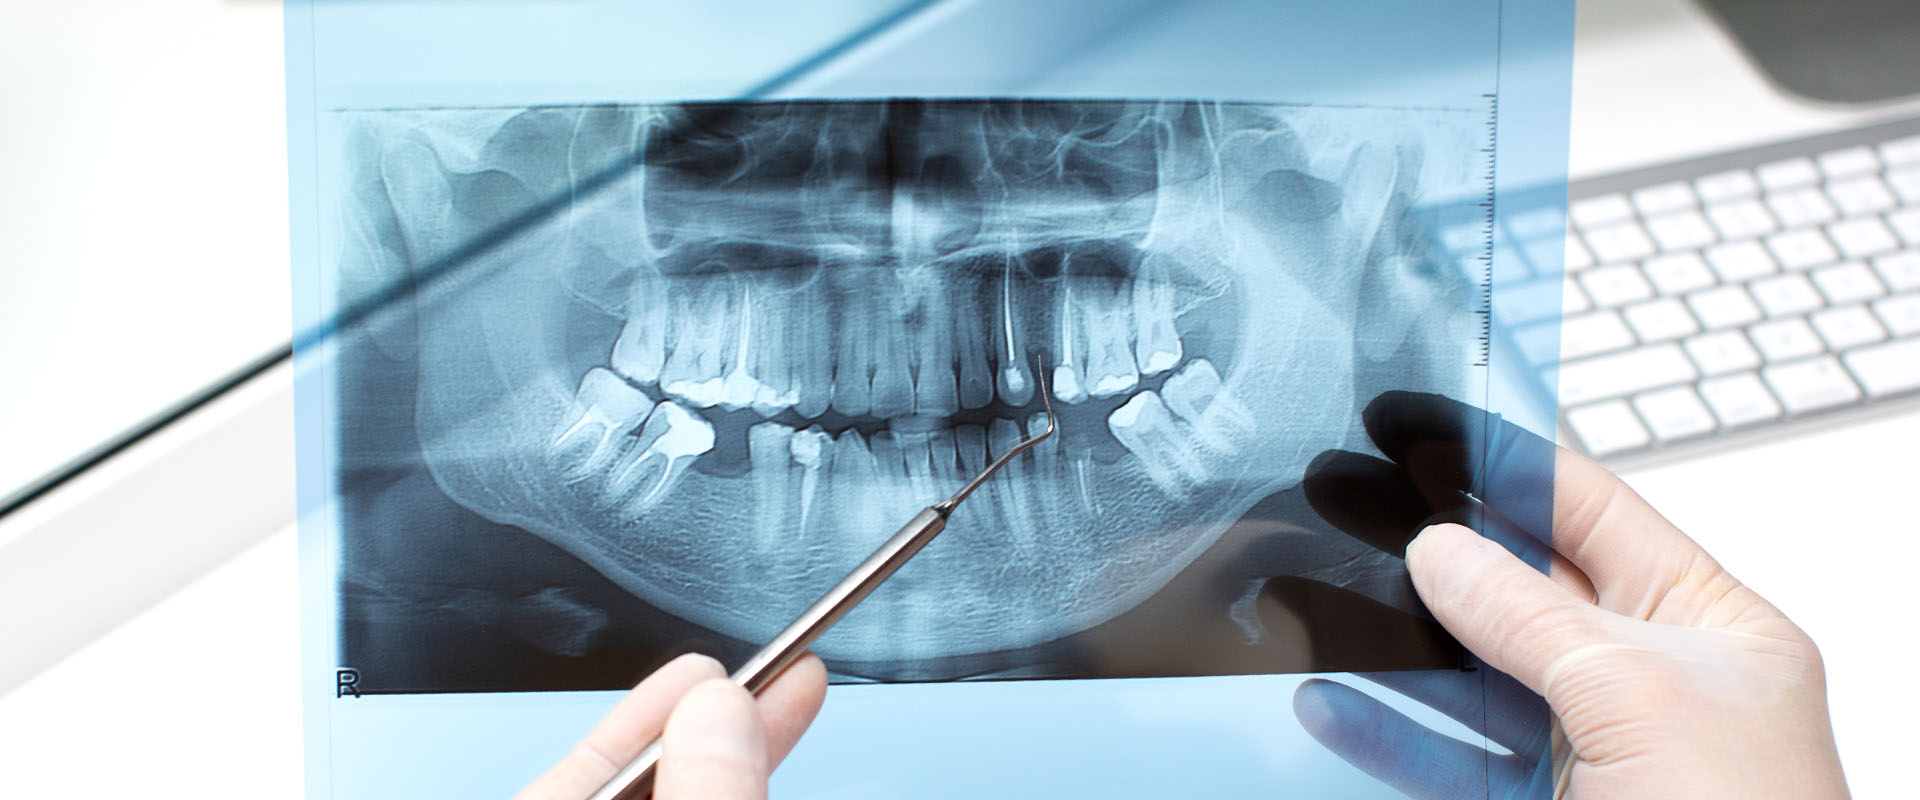

Zdjęcie pantomograficzne /panoramiczne/ – to podstawowe badanie radiologiczne, na podstawie którego możemy ocenić warunki kostne do wprowadzenia implantów dentystycznych.

Podstawowym, najistotniejszym czynnikiem dla powodzenia leczenia implantologicznego jest wystarczająca ilość kości, pozwalająca na wprowadzenie do niej wszczepów o odpowiedniej średnicy i długości. Jej ilość i jakość rzutuje na długoczasowość leczenia i właściwe efekty protetyczne i kosmetyczne. Badania radiologiczne wykonane przed zabiegiem pozwalają nam na dokładną ocenę warunków kostnych i położenia struktur anatomicznych w obrębie szczęk.

Wykonane w odpowiednie skali /np.1:1 lub 1:1,3/ pozwala nam na wykonanie dokładnych pomiarów interesujących nas struktur. Często, przed wykonaniem zdjęcia pantomograficznego do celów implantacyjnych umieszczamy w jamie ustnej tzw. markery, czyli metalowe kulki o średnicy 5 mm, które w obrazie rentgenowskim nie ulegają zniekształceniu. Dzięki nim, stosując później odpowiedni przelicznik związany ze skalą wykonanego zdjęcia mamy możliwość wykonania bardzo precyzyjnych obliczeń.

zdjęcie pantomograficzne